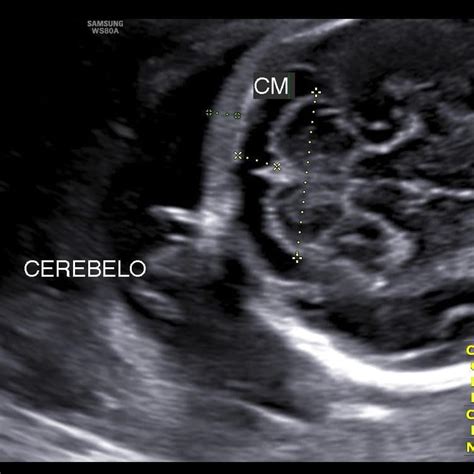

El cerebro

La ecografía también permite visualizar estructuras cerebrales como el cerebelo, responsable de la coordinación y el equilibrio muscular. Su forma y desarrollo son importantes para identificar defectos del tubo neural, como la espina bífida, que puede afectar la médula espinal y la columna vertebral.